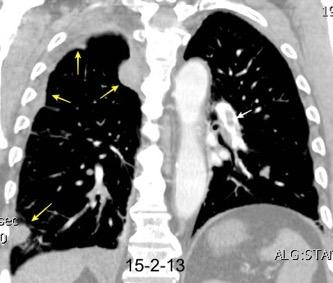

Tromboembolismo pulmonar.

Frecuencia del derrame:

Rx: 32%. TC: 47%

Unilateral. 85%

< 1/3 del hemitórax: 90%

Todos exudados

58% con eritrocitos

21% tabicación lo que causa demora en el diagnóstico

TEP. Empiema pleural. Atelectasia redonda

Porcel JM et al. Analysis of pleural effusions in acute pulmonary embolism: radiological and pleural fluid data from 230 patients. Respirology 2007/ Iguchi T et al. Desquamation of the subpleural lung parenchyma caused by empyema after pulmonary embolism: A case report. Respirol Case Rep. 2022 .